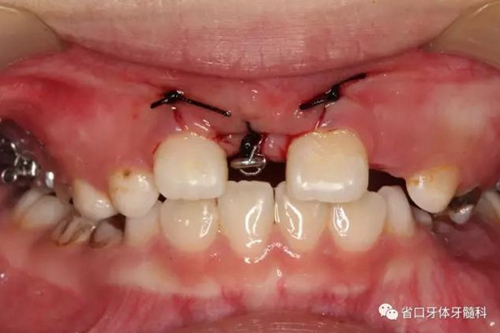

治療過程:安裝上頜腭托式牽引裝置,局麻下翻瓣、開窗、暴露11牙冠,在牙齒腭側(cè)面粘接附件進(jìn)行輕力牽引,縫合。定期(2-3周)復(fù)診加力,待11唇面暴露后粘接前牙托槽,擴(kuò)展間隙的同時(shí)繼續(xù)進(jìn)行牽引、排齊。6個(gè)月后牽引到位,術(shù)后牙齒位置和牙髓活力均正常,牙齦形態(tài)良好,X線片顯示11牙軸基本正常,牙根發(fā)育良好。牽引結(jié)束后拆除前牙固定矯治器,由于前磨牙已開始替換,因此繼續(xù)戴用腭托進(jìn)行間隙保持。

11開窗,粘接附件進(jìn)行牽引